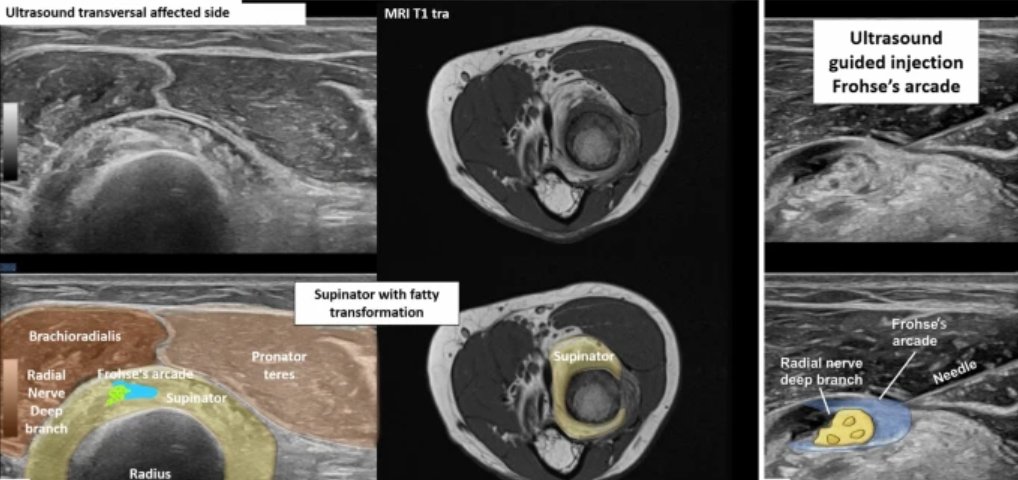

Advanced high-resolution musculoskeletal ultrasound: a histology- and anatomy-guided approach for improved imaging of the shoulder. Part 2: Anterior and lateral shoulder FREE DOWNLOAD: jultrason.pl/artykul.php?a=… FREE DOWNLOAD Part 1: x.com/Rheumatology/s… I would like to thank

Advanced high-resolution musculoskeletal ultrasound: a histology- and anatomy-guided approach for improved imaging of the shoulder.

Part 2: Anterior and lateral shoulder

FREE DOWNLOAD:

jultrason.pl/artykul.php?a=…

FREE DOWNLOAD Part 1:

x.com/Rheumatology/s…